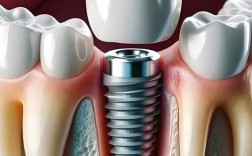

种植牙后,最终安装在种植体(植入牙槽骨的钛钉)上、模拟自然牙形态和功能的修复体,通常被称为牙冠或修复体,选择哪种牙冠材料,主要取决于以下几个因素:🦷主要的牙冠材料类型全瓷牙冠:优点:美观度最高:颜色、通透度、光泽度最接近天然牙,尤其在前...